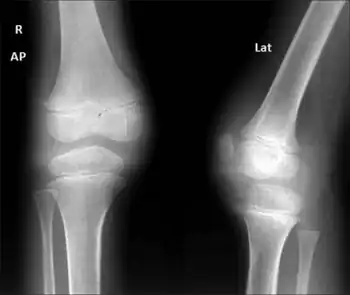

| Three-year 3-month-old girl child with CACP syndrome. Coronal STIR image of both knees (on 3T system) shows large effusions. Small intraosseous cysts are identified along the medial femoral condyle (arrows) | |

Large acetabular cysts are common in this condition.[2] Other features include periarticular osteopenia, squaring of metacarpals and phalanges and bilateral joint effusions.